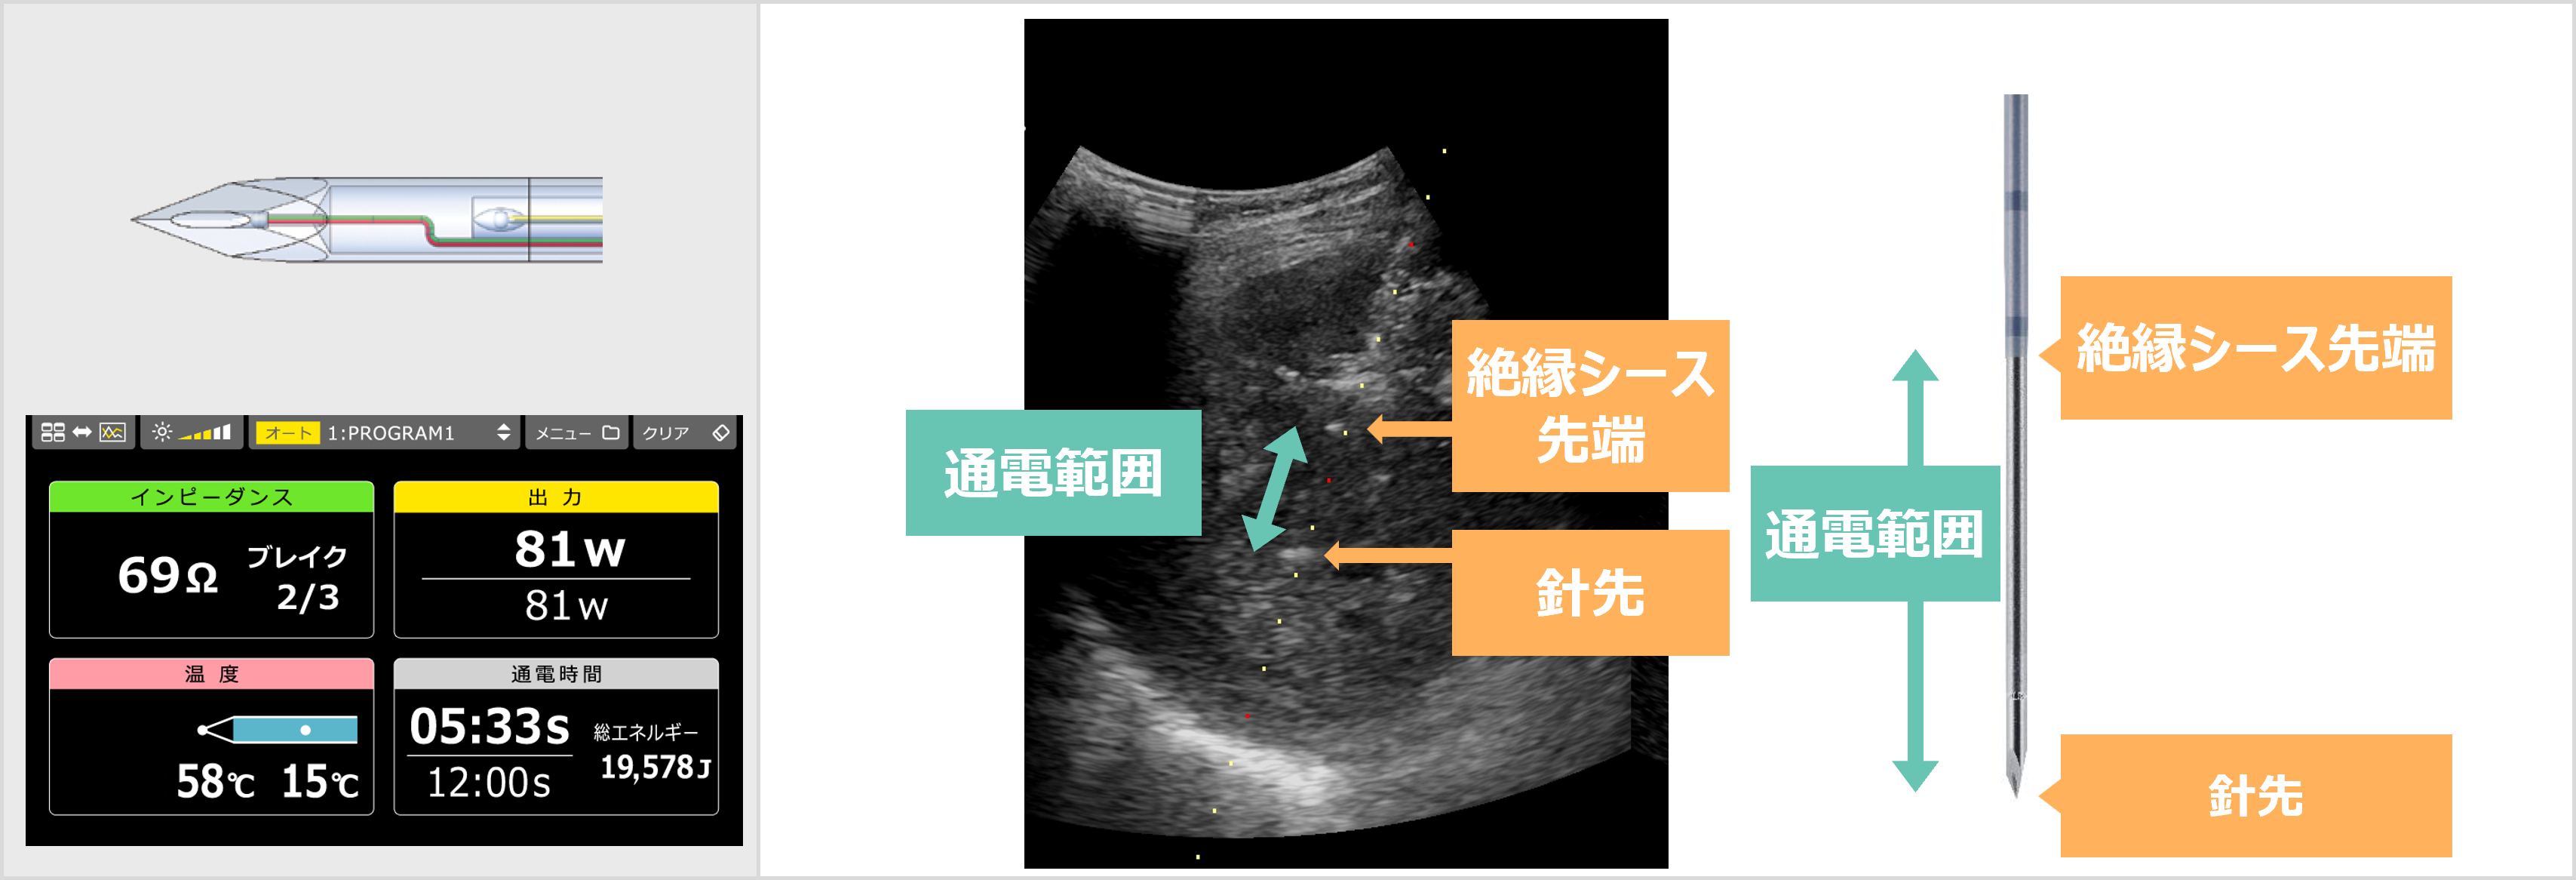

・Multidisciplinary approachによる肝癌治療―Transradial access TACE(R2V)と可変型電極(arfa)による低侵襲治療への期待―

川村 祐介 先生(埼玉医科大学総合医療センター 消化器・肝臓内科)